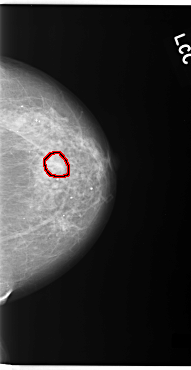

C_0093_1.LEFT_CC

LEFT_CC LINES 5912 PIXELS_PER_LINE 3048 BITS_PER_PIXEL 12 RESOLUTION 50 OVERLAY

FILE: C_0093_1.LEFT_CC.OVERLAY

TOTAL_ABNORMALITIES 1

ABNORMALITY 1

LESION_TYPE CALCIFICATION TYPE AMORPHOUS DISTRIBUTION CLUSTERED

ASSESSMENT 5

SUBTLETY 4

PATHOLOGY MALIGNANT

TOTAL_OUTLINES 1

BOUNDARY